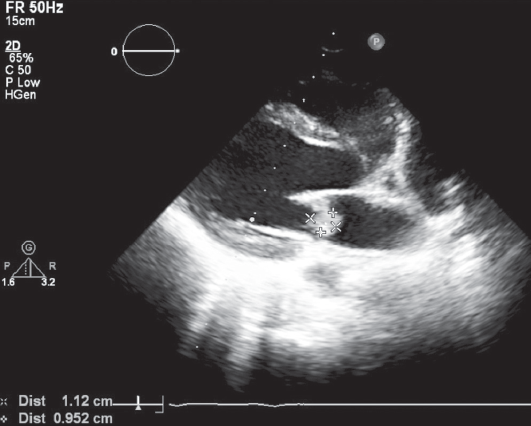

The optimal time for surgery on the heart valves in patients with active infectious endocarditis (IE) is still controversial. It is a well known fact that cerebral, coronary or renal thromboembolism is the most common cause of death in patients with left-sided IE. Thromboembolism can develop before the appearance of clinical manifestations of the destruction of the valvular apparatus of the heart. Currently, early surgical intervention is considered as the most effective method of treatment of many forms of active left-sided IE. Early surgery involves performing surgical correction until the completion of a full antibiotics course. We present the clinical case of early surgical correction of the patient (A., 16 years) with mitral valve infectious endocarditis. The disease was acute, with recurrent embolisms to the right kidney with infarction and to the left clavicle with osteomyelitis. Surgical intervention was performed as a matter of urgency; surgical access – right-sided anterolateral thoracotomy. The girl was operated on the 4th day of the hospitalization to our hospital. However, time of treatment was lost at the prehospital stage and rapid mitral valve destruction did not allow to repair the valve. Therefore, the mitral valve replacement was performed. The postoperative period was favorable. On the 3rd day after the operation, the girl was transferred to the cardiology department. On control ECHO after 3 years: myocardial contractile function is good, EF 65%, the function of the MV prosthesis is not impaired.